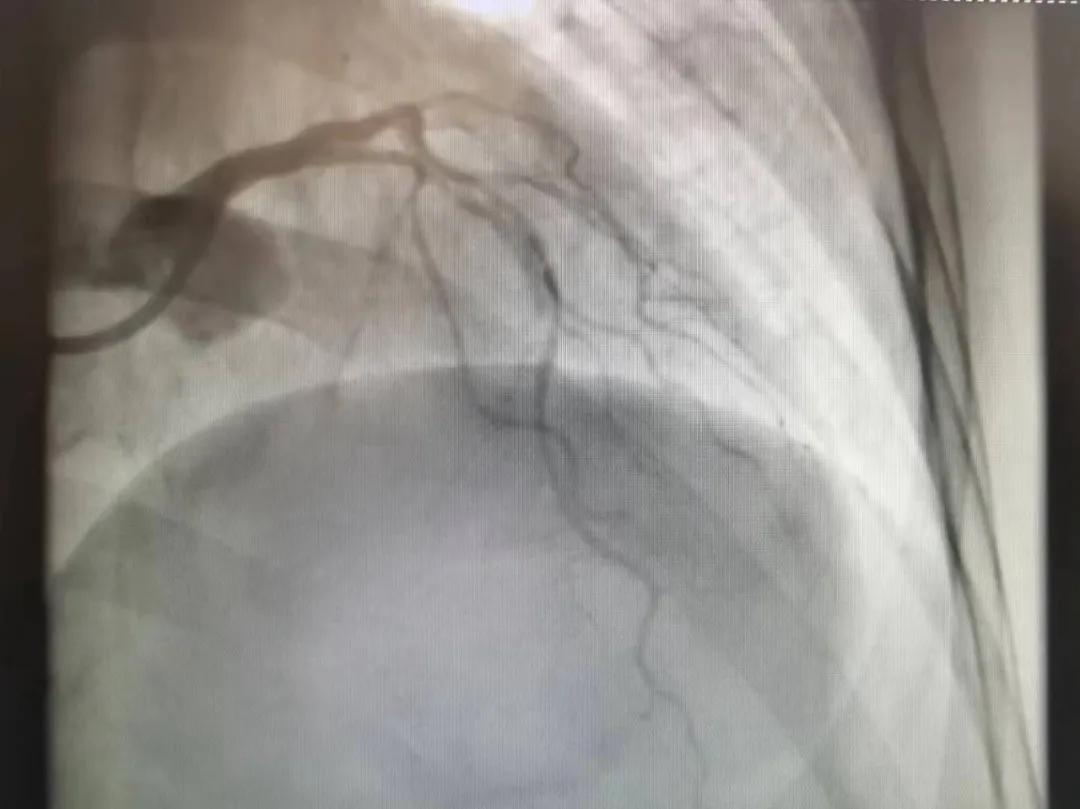

術(shù)后

王瑾院長(zhǎng)和李慧新主任帶領(lǐng)介入團(tuán)隊(duì)充分評(píng)估,決定行前降支冠狀動(dòng)脈鈣化病變旋磨術(shù),術(shù)中應(yīng)用1.5mm旋磨頭,以15萬(wàn)-17萬(wàn)轉(zhuǎn)/分速度共對(duì)病變旋磨3次,累計(jì)旋磨時(shí)間60秒,后復(fù)查造影示鈣化明顯減輕,為后續(xù)操作創(chuàng)造了良好條件,隨后應(yīng)用預(yù)擴(kuò)張球囊、切割球囊再次處理病變,并順利植入支架1枚,復(fù)查造影顯示支架膨脹及貼壁良好,無(wú)夾層、血腫、慢血流等情況,手術(shù)順利完成?;颊咝g(shù)后無(wú)不適,胸悶、胸痛癥狀明顯緩解,順利出院。